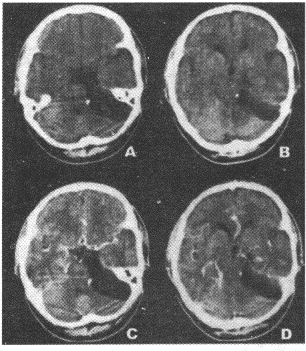

13.女性,43歲。左側(cè)面部不適感1年。CT圖像如圖所示,需要進行鑒別診斷的疾病包括

正確答案:AD 解題思路:膽脂瘤為起源于外胚層的先天性腫瘤,是胚胎早期神經(jīng)溝封閉時,皮膚外胚層的剩件留下來發(fā)展而成。